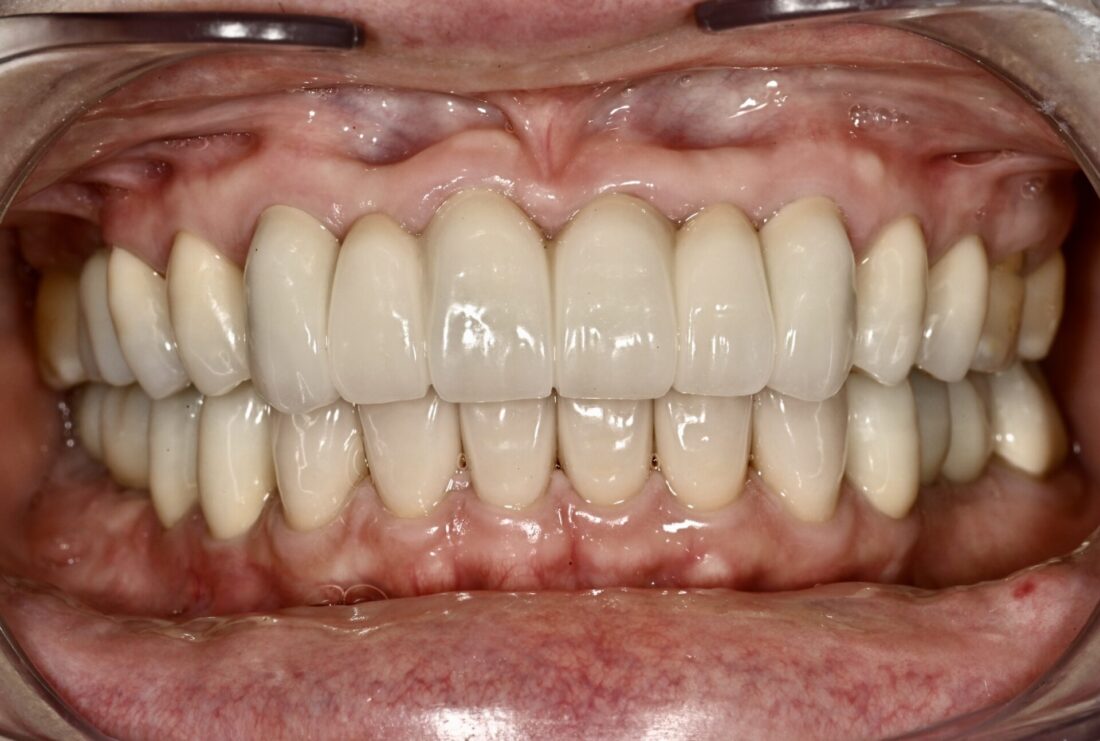

術後(3年・メインテナンス中)

どちらが良いか判断はお任せします。

時間もかかりましたが、患者さんは大変満足されています。